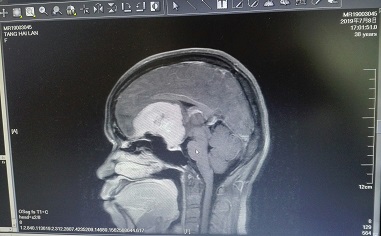

2019年7月经朋友介绍,唐女士来到四川友谊医院神经外科就医,我院神经外科学科带头人(原四川大学华西医院神经外科主任)游潮教授仔细询问病情,阅片后,考虑唐女士为:前颅窝底脑膜瘤,属于良性肿瘤。建议唐女士尽快手术治疗,否则肿瘤进一步长大,唐女士可能双眼失明。这样的消息如雷轰顶,唐女士找到亲戚朋友借钱,终于筹到了5万元医疗费用,来到四川友谊医院住院治疗。完善术前准备,复查颅脑核磁共振平扫及增强检查:前颅窝底占位性病变,大小约为5.1*5.6*3.9cm,形态规则,脑膜瘤可能性大。于2019年7月11日在全麻下行前颅窝底脑膜瘤开颅肿瘤切除术,在游潮教授的带领下,神经外科团队经过12小时的奋战,术中全部切除肿瘤。术后组织病检:脑膜瘤,混合型。WHO:Ⅰ级。经过术后20天的康复,于2019年7月30日治愈出院。出院时唐女士嗅觉较前好转,双眼视力正常,四肢活动正常,无手术并发症。

手术前